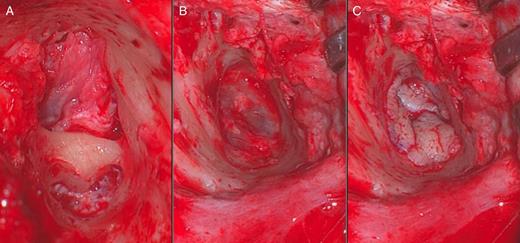

To improve his hearing, he underwent a left external auditory canaloplasty. At operation, the skin overlying and immediately lateral to the posterior tympanic membrane was thickened and fibrosed, confirming the radiological findings. A 4-mm smooth bar of bone was found to be traversing the deep external auditory canal immediately lateral to the inferior tympanic membrane (Fig. 2). The calibre of the external auditory canal was otherwise normal and symmetrical with that of the right ear. The bony bar was drilled away taking care not to damage the tympanic membrane. Upon peeling off the remaining mass of fibrosis, the underlying tympanic membrane was intact. A partial-thickness graft harvested from postauricular skin was used to cover the de-epithelialized tympanic membrane and exposed bone of the deep external auditory canal. Postoperative audiometry showed an improvement in conductive hearing with a pure tone average of 55 dB.

Intraoperative images showing the horizontal bony bar (A), view of an intact tympanic membrane post-drilling (B) and placement of a partial-thickness skin graft (C).